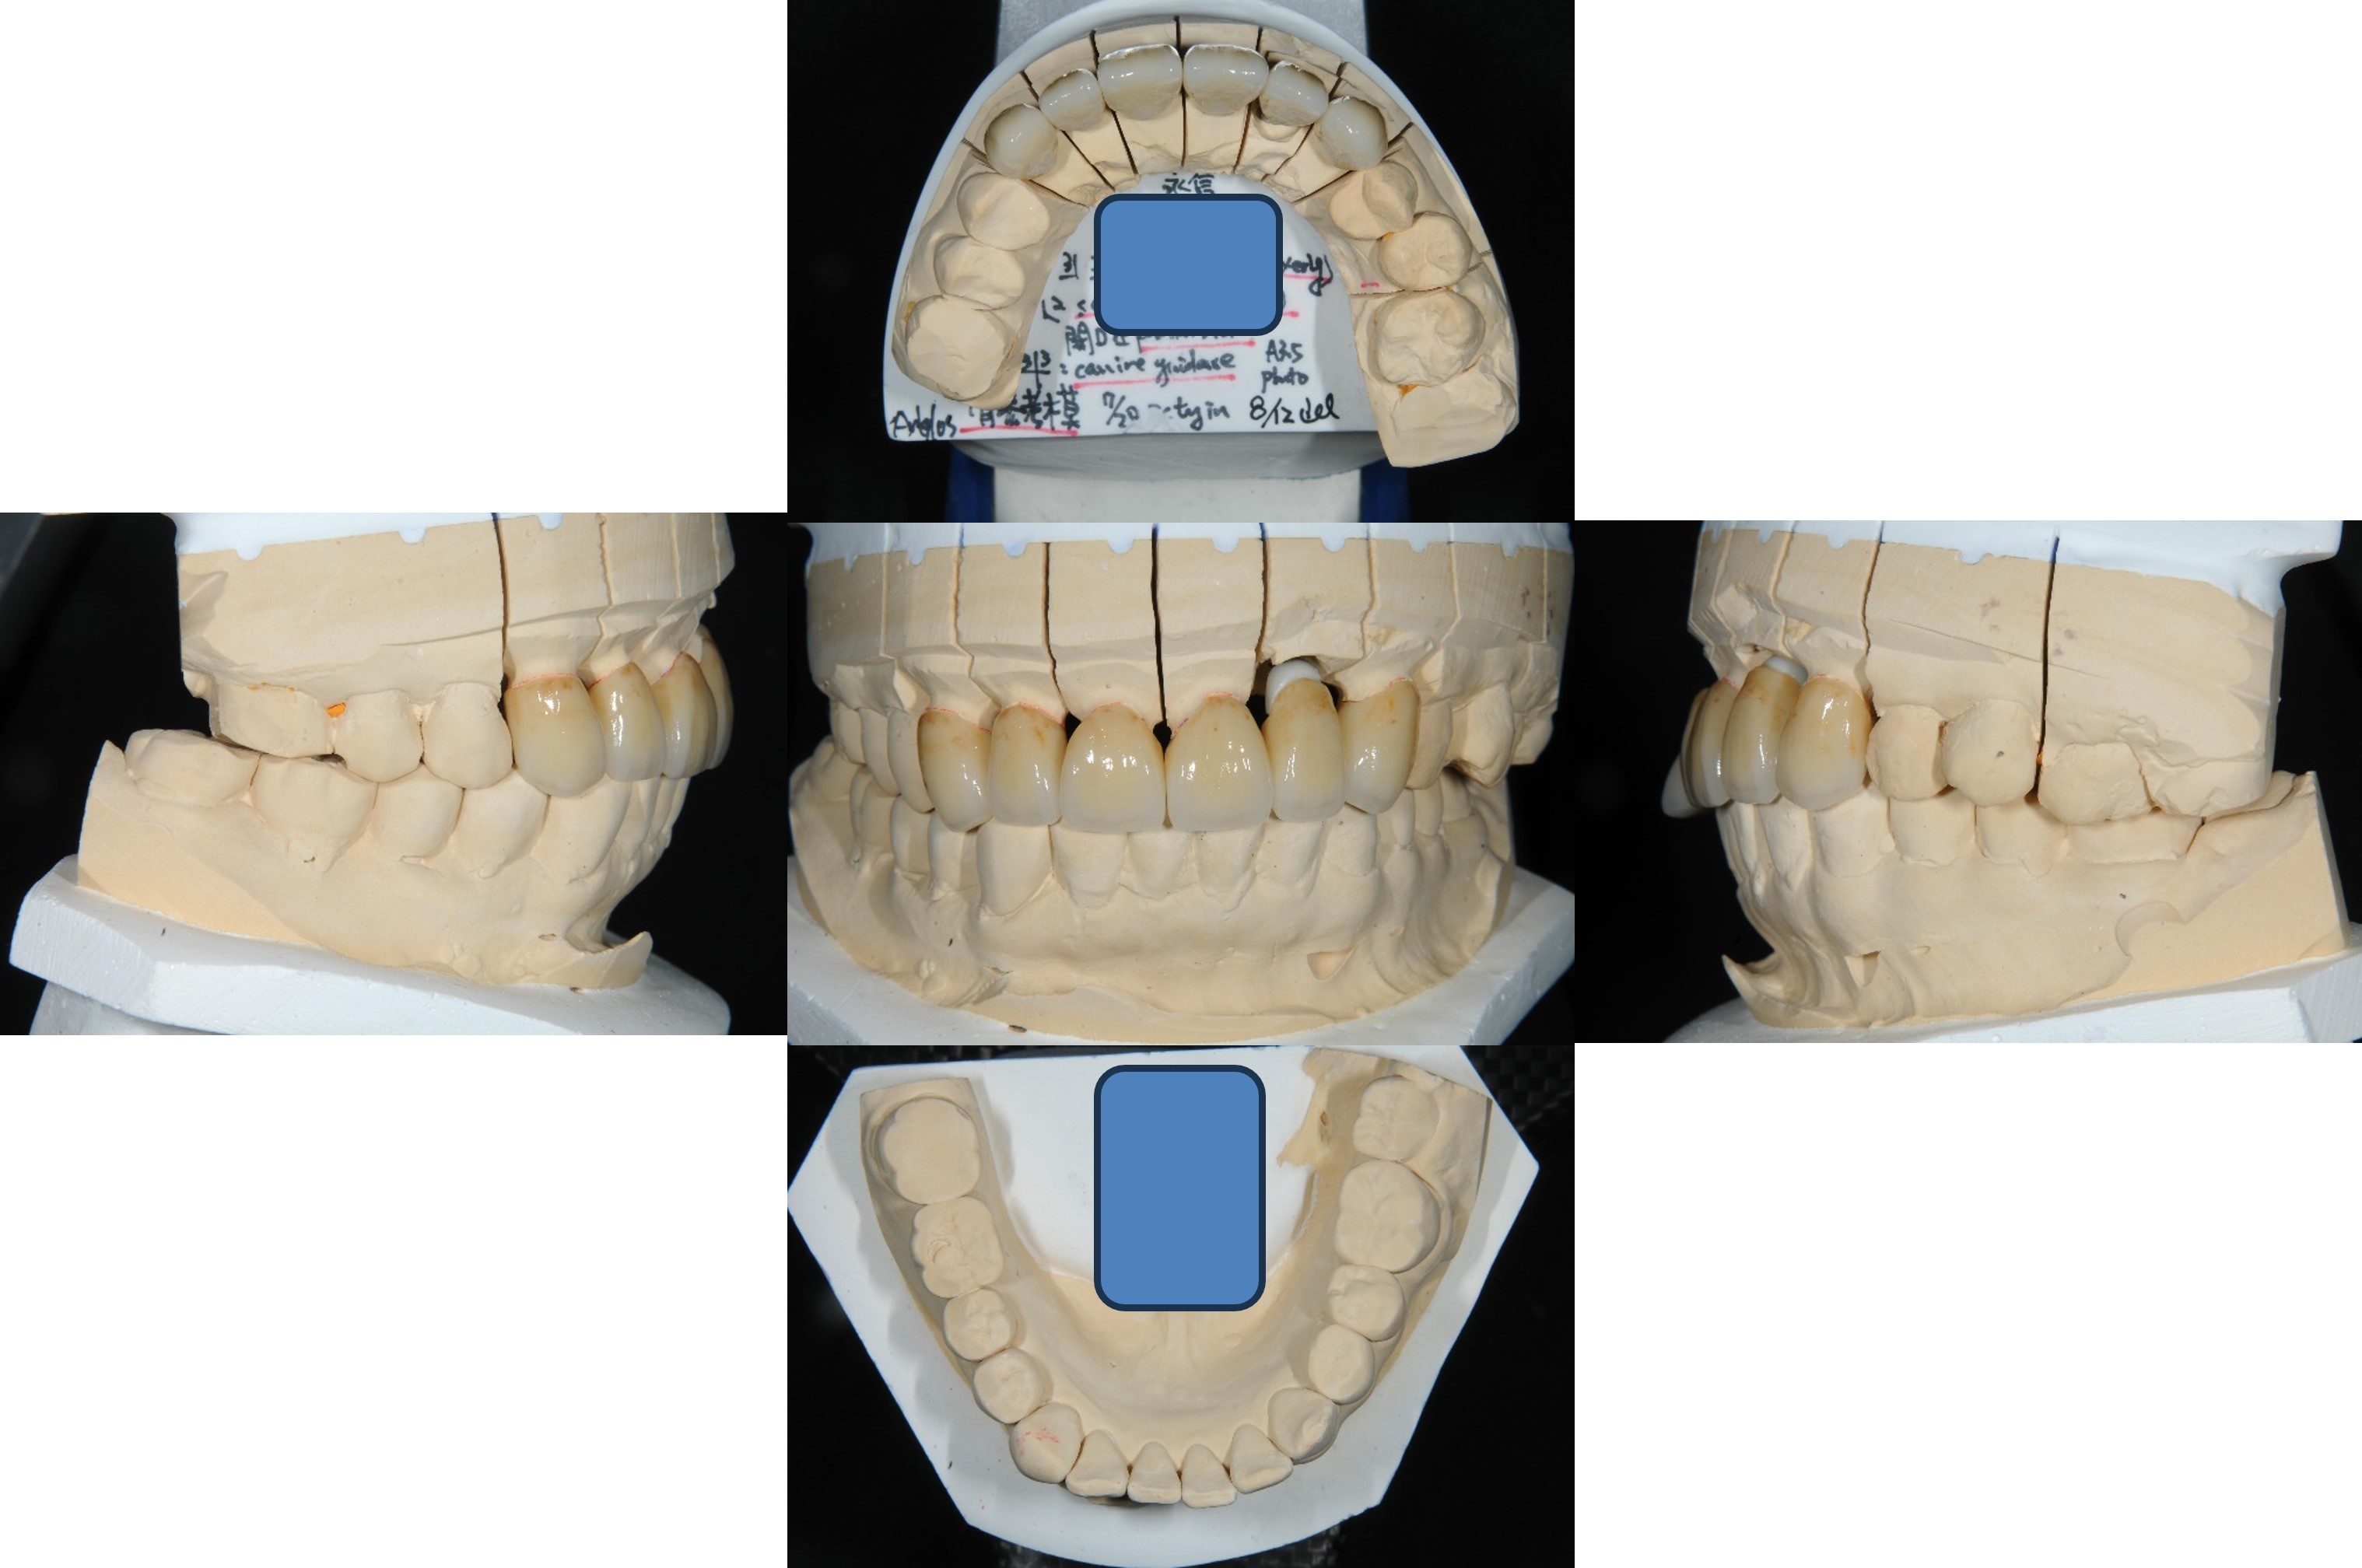

面弓轉移,上咬合器

咬合器上製作瓷牙